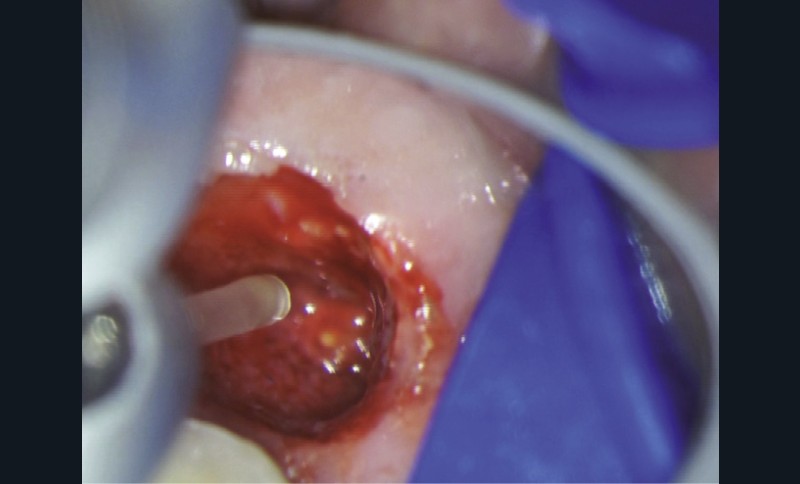

Chirurgie endodontique

L’Er:YAG a également sa place en chirurgie endodontique. En mode ablatif, il permettra l’élimination des tissus de granulation et des tissus fibro-kystiques en assurant la stérilisation de la crypte osseuse ainsi formée.

La résection apicale et la préparation a retro exposent des canaux et des tubulis dentinaires infectés, qui pourront là aussi, être décontaminés par l’action du laser Er:YAG et de l’eau distillée [36].

Les espaces non accessibles à l’instrumentation conventionnelle pourront, là aussi, être débridés et stérilisés (fig. 11a à f). Cette procédure semble accélérer de manière très significative les processus de régénération osseuse (fig. 11f).